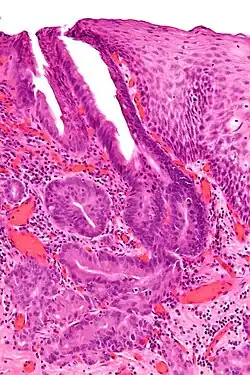

Oesophagogastric junctional adenocarcinoma

Oesophagogastric junctional adenocarcinoma (OGJ adenocarcinoma) is a cancer of the lower part of the oesophagus with a rising incidence in Western countries.[1] This disease is often linked to Barrett's oesophagus.